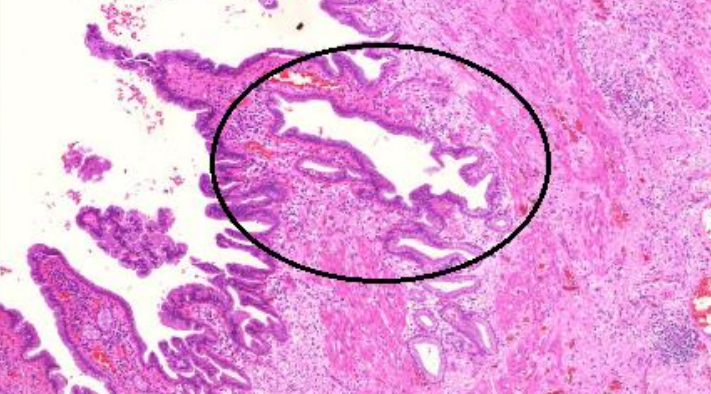

2. Colecistite crônica (A523)

1. Fibrose

1. Hipertrofia muscular

1. Seio de Rokitanski Aschoff

1. Invaginações da camada mucosa